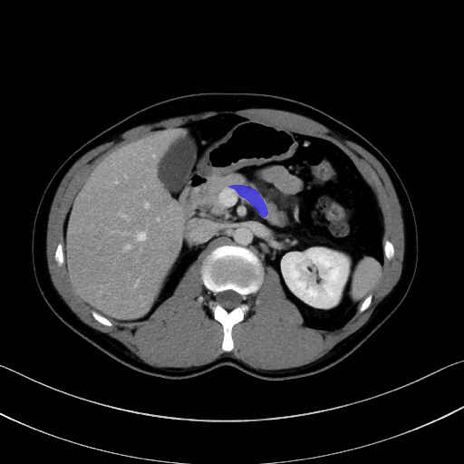

脾静脈の画像解剖

■起始:脾門で脾静脈枝が合流して本幹を形成。

■走行:膵体尾部の後面溝を右走し、膵頸部の後方で上腸間膜静脈(SMV)と合流して門脈を形成。

■主な流入枝:短胃静脈・左胃大網静脈・膵静脈、そして下腸間膜静脈(IMV)(変異あり)。